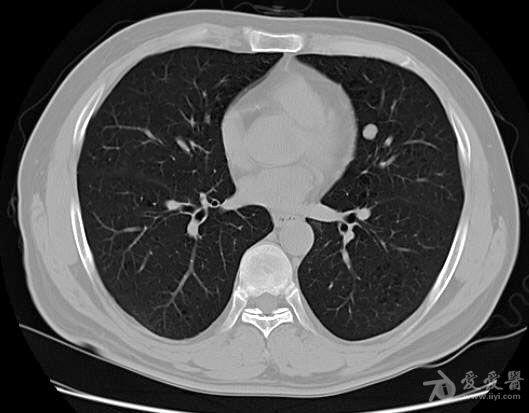

青年男性胸部结节ct检查

图片尺寸529x413